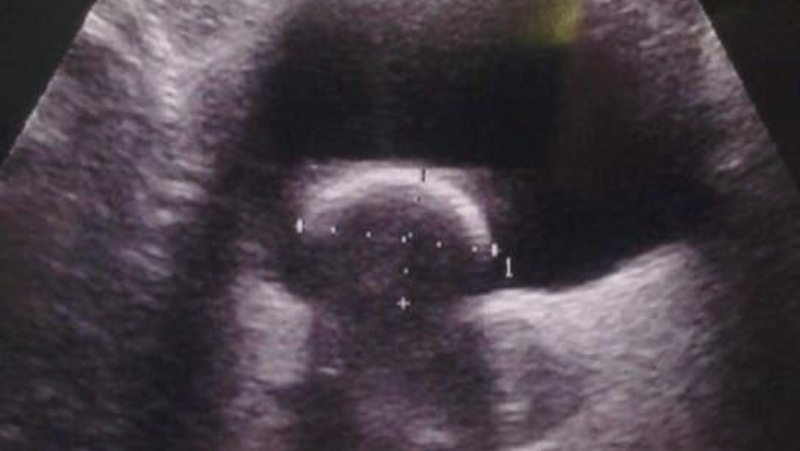

Камень вовремя обнаружили во время УЗИ-диагностики Фото: БСМП г. Ставрополя

Образование крупных камней у двухлетних детей — очень редкое явление. Но именно эта беда и постигла маленькую ставропольчанку. Камень размером 2,5x2 см обнаружила в мочевом пузыре ребёнка завотделением УЗИ городской больницы скорой помощи Ставрополя Инна Стригина. Медлить было нельзя, и за дело взялись урологи.